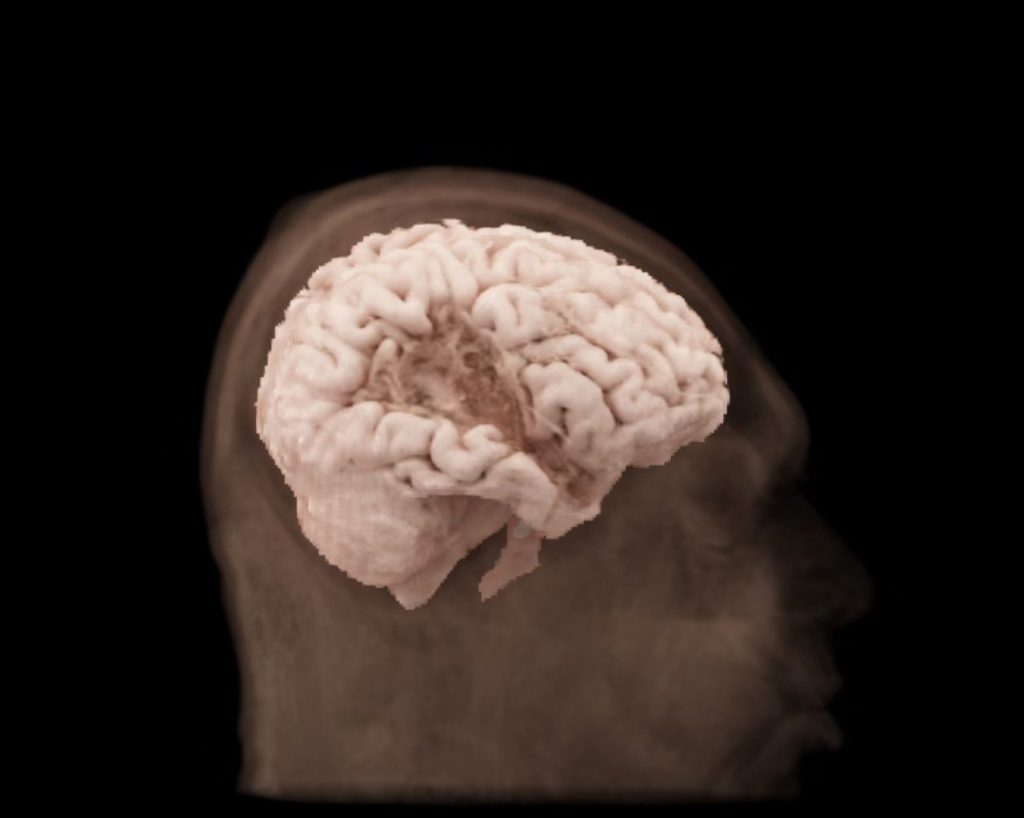

Stroke: Recovery can be significantly slowed without access to nutrient-dense foods that reduce inflammation and support brain repair. Disparities mean higher rates of death and long-term disability for individuals in low-income areas.

Traumatic Brain Injury (TBI): The brain’s healing process requires extra energy and specific nutrients. Without access to these “building blocks,” recovery from a concussion or more severe injury can be incomplete, leading to chronic issues like brain fog and fatigue.

Dementia & Alzheimer’s Disease: Research strongly links diet to the risk and progression of dementia. A diet lacking brain-protective nutrients can accelerate cognitive decline, a challenge made worse in communities without access to fresh, healthy food.